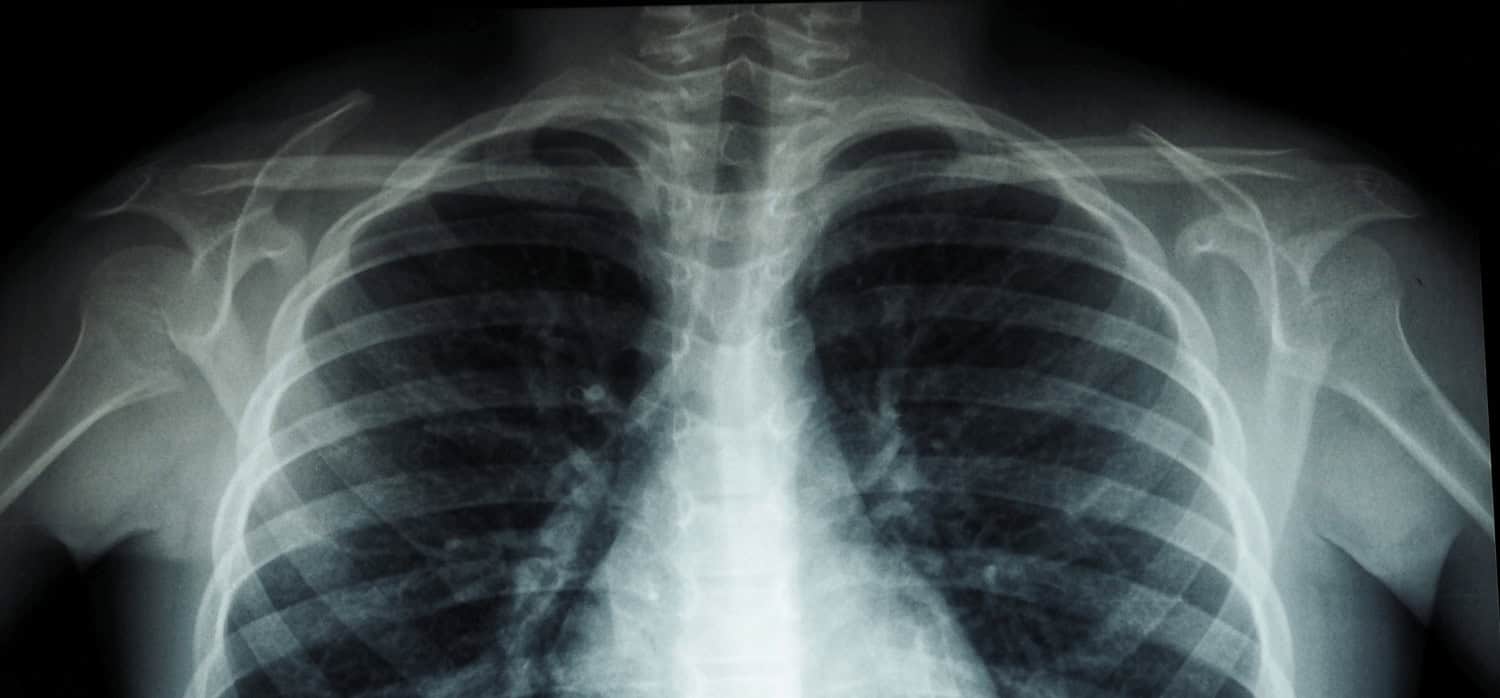

Deep AI imaging diagnostics help doctors prioritise care By StephFeltham 18th February 2022 South African startup Envisionit has developed technology that can scan more than 2,000 x-rays per minute This content is for members only. Please click here to view the full article.